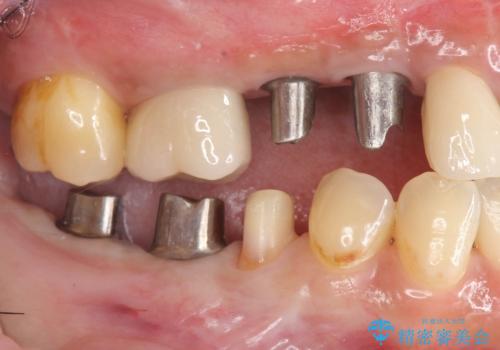

- 銀歯だらけの口腔内で将来歯がなくなるのではないかと不安になり、精査、治療を求めて来院されました。

歯周病や虫歯・強度の問題がありながらも無理やり残していた長期的な予後の見込めない歯を抜去し、インプラントを用いてしっかりと噛めるような口腔内環境の確立を目指します。

- 176万円(インプラント×4・チタンカスタムアバットメント×4・ジルコニアクラウン×4・仮歯×4)費用は治療当時の料金となります

見た目が白くなり喜んでいただけただけでなく、しっかりとした噛めるようになり食事を不安なく楽しんでいただけるようになりました。